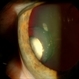

- inflammation, chronic uveitis

- 44-year-old white female, chronic uveitis, 20/60; 20/400.